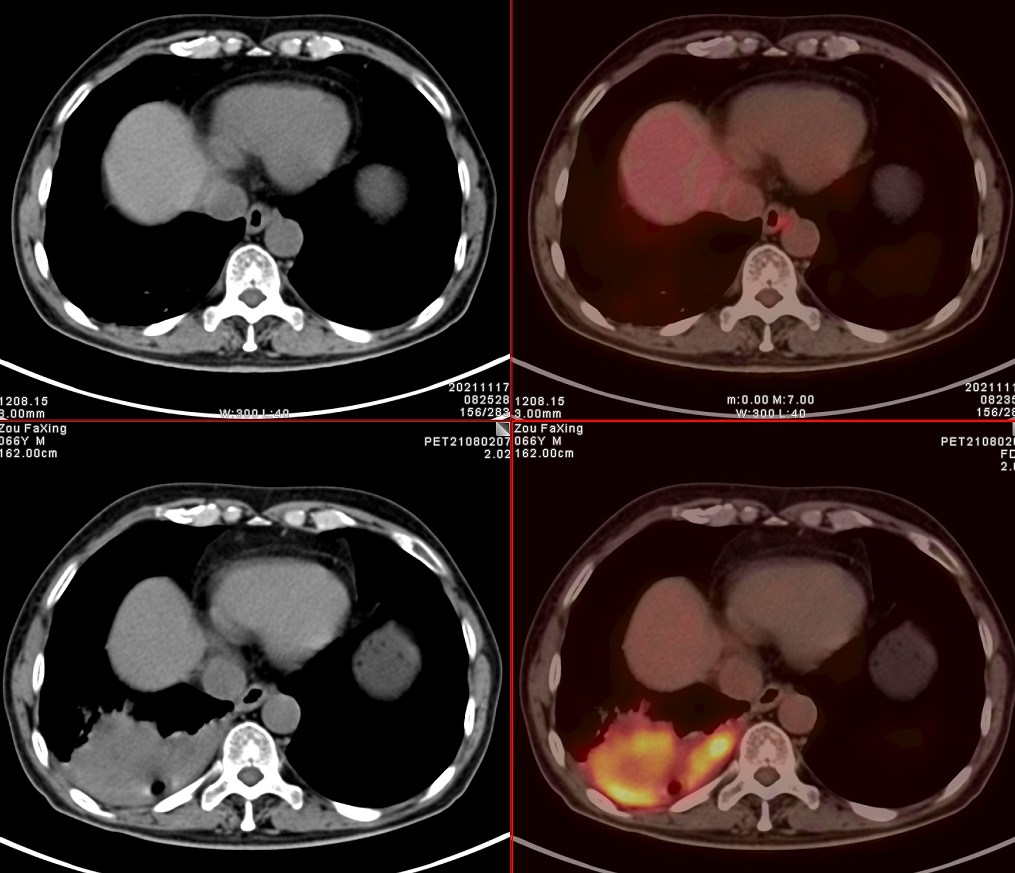

依据影像学分期,该患者后续进行了综合治疗:免疫+化疗+靶向治疗,其中化疗3期,免疫治疗2期及靶向治疗。3个月后患者再次进行了PET/CT检查,对治疗效果进行了评估。2021年11月PET/CT检查结果:

肿瘤病灶明显缩小、实性成分明显减少,肿瘤FDG代谢明显减低,相邻胸膜浸润明显改善,已经没有胸水征象。另外,全身其他部位未见明确转移性病变。

上面两张为治疗后,下面为治疗前

复查后PET/CT诊断:右肺下肺癌综合治疗后,肿瘤病灶明显缩小,FDG代谢明显减低,相邻胸膜未见高代谢病变,考虑肿瘤治疗后疗效显著,仅少量肿瘤活性残留。

根据我们PET/CT诊断,患者第二天就进行残余右肺癌病灶的手术切除。通过上述综合治疗,将一个原本没有手术机会的患者从死神的手中抢回来。虽然愈后情况有待进一步观察,但是通过PET/CT评价,患者病情明显好转,身体素质明显好转,生活质量明显提高,将不可能变为可能。后续进一步疗效,我会密切关注,后期随访再和大家分享。